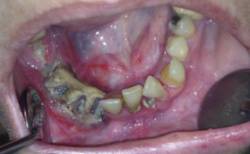

En este sentido, algunos autores han encontrado una asociación entre enfermedad periodontal y osteoporosis. Y es precisamente en el empleo de los fármacos que se utilizan para el tratamiento de esta enfermedad, los bifosfonatos, ampliamente difundidos entre la población, donde ha aparecido un nuevo proceso patológico, la osteonecrosis maxilar o mandibular.

Imagen en alta resolución. Este enlace se abrirá mediante lightbox, puede haber un cambio de contextoLa Revista Española de Cirugía Oral y Maxilofacial (RECOM), publicó hace unos años un artículo, "Diagnóstico, prevención y tratamiento de la osteonecrosis de los maxilares por bisfosfonatos, "donde se establecen una serie de recomendaciones de la Sociedad Española de Cirugía Oral y Maxilofacial (SECOM) a tener en cuenta cuando vamos a tratar la boca de pacientes que toman bifosfonatos orales e intravenosos. Los profesionales que trabajamos en maxilofacial debemos conocer los protocolos de profilaxis que van publicándose y estar atentos a sus actualizaciones. Este puede ser un punto de partida para complementar con publicaciones más recientes y poder afrontar con seguridad el tratamiento de nuestras pacientes", señala el doctor José Luis Cebrian.